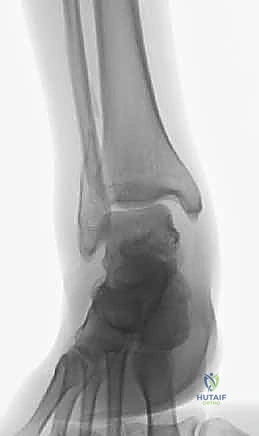

2. الأشعة السينية (X-rays)

هي الخطوة الأساسية. يتم أخذ صور بأوضاع مختلفة (أمامي، جانبي، ومائل - Mortise view) لتحديد مكان الكسر، درجة التفتت، ومدى تباعد العظام.

الكسر ثنائي الكعب (Bimalleolar Fracture) يعني ببساطة انكسار كل من الكعب الإنسي (الظنبوب) والكعب الوحشي (الشظية) في نفس الوقت.